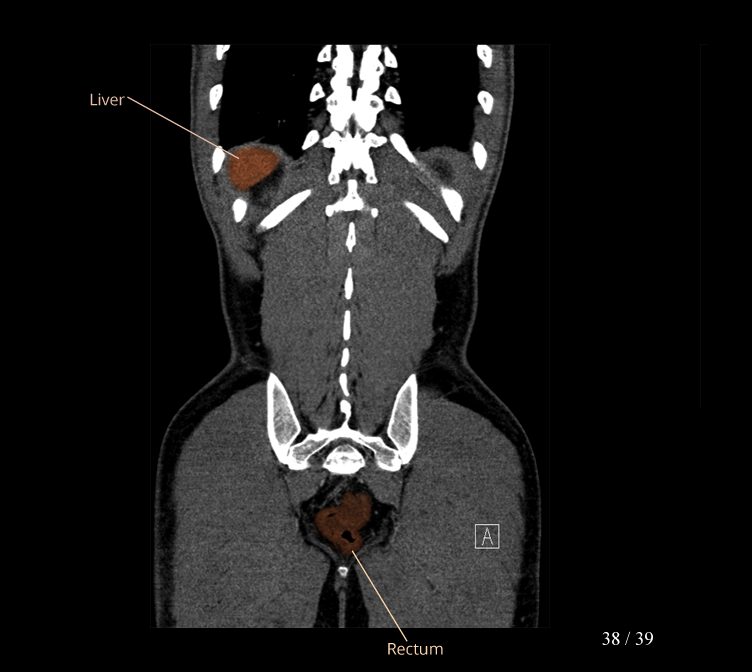

Body

Covers abdominal CT anatomy.